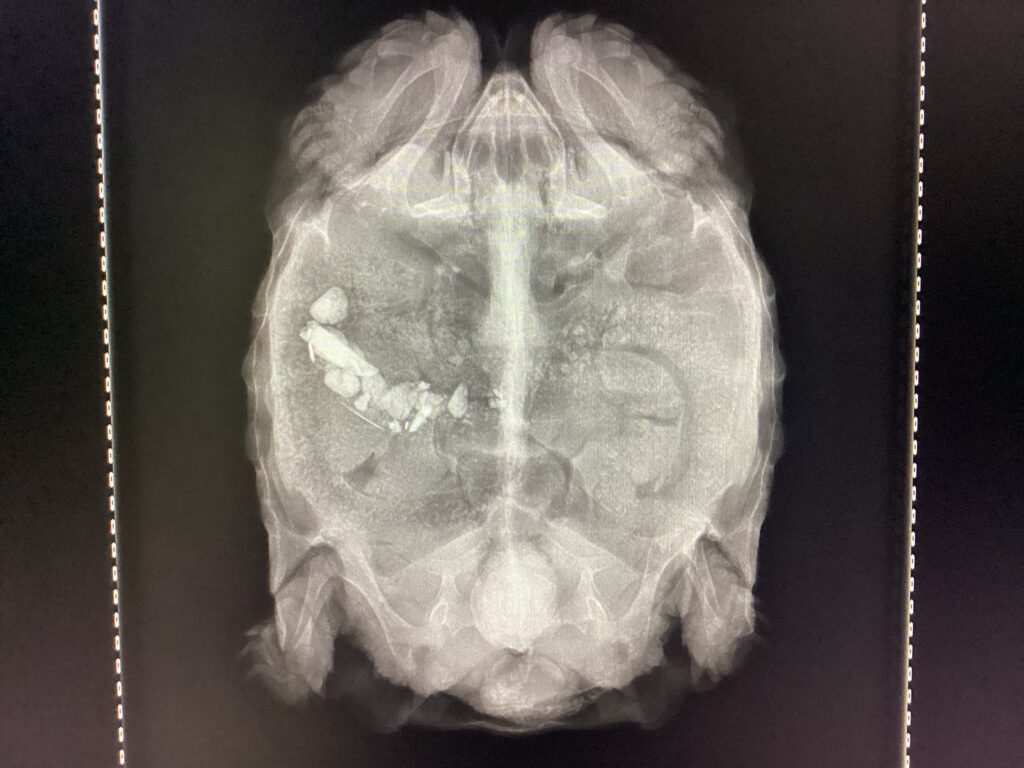

写真の子は総排泄腔に結石ができたことで排泄が困難になっており、便秘になっていることがレントゲンから分かります。この子は小石や砂利を誤食してしまってもいます。

幸いこの子は外からのアプローチが可能であったため、破砕して摘出を行いましたが、場合によっては開腹手術が必要になるため注意が必要です。